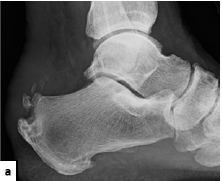

While many data points are subjective in regard to pain relief in trials involving ESWT, Vahdatpour and colleagues examined the ultrasonographic appearance of plantar fascial thickness in their 2012 study.11 After three weekly treatments of focused shockwave therapy, the authors noted significantly decreased plantar fascial thickness in the ESWT group and slightly increased plantar fascial thickness in the placebo group. Both treatment groups noted improvement of pain but there was significantly more pain reduction exhibited in the ESWT group.

In a 2020 study that included 60 patients with plantar fasciitis, Soliman and coworkers looked at PRP injection versus ESWT.12 While both treatment groups had significant improvement of pain and function, the study authors concluded that ESWT led to this improvement earlier in the study points and was more effective in patients who had a noted calcaneal spur.12